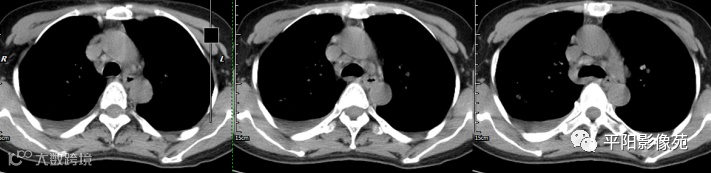

腹部增强 动脉期